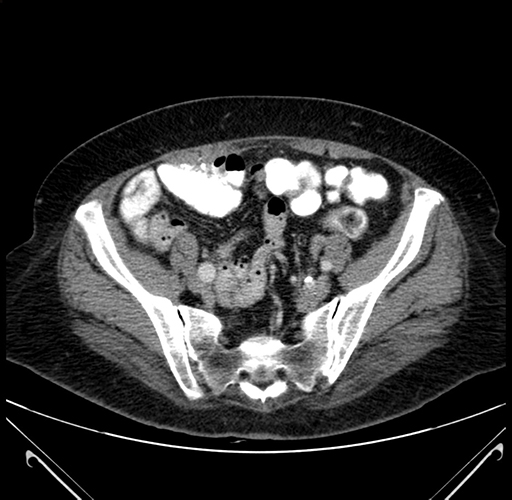

Pre-Chemo: Axial Venous

Axial Venous